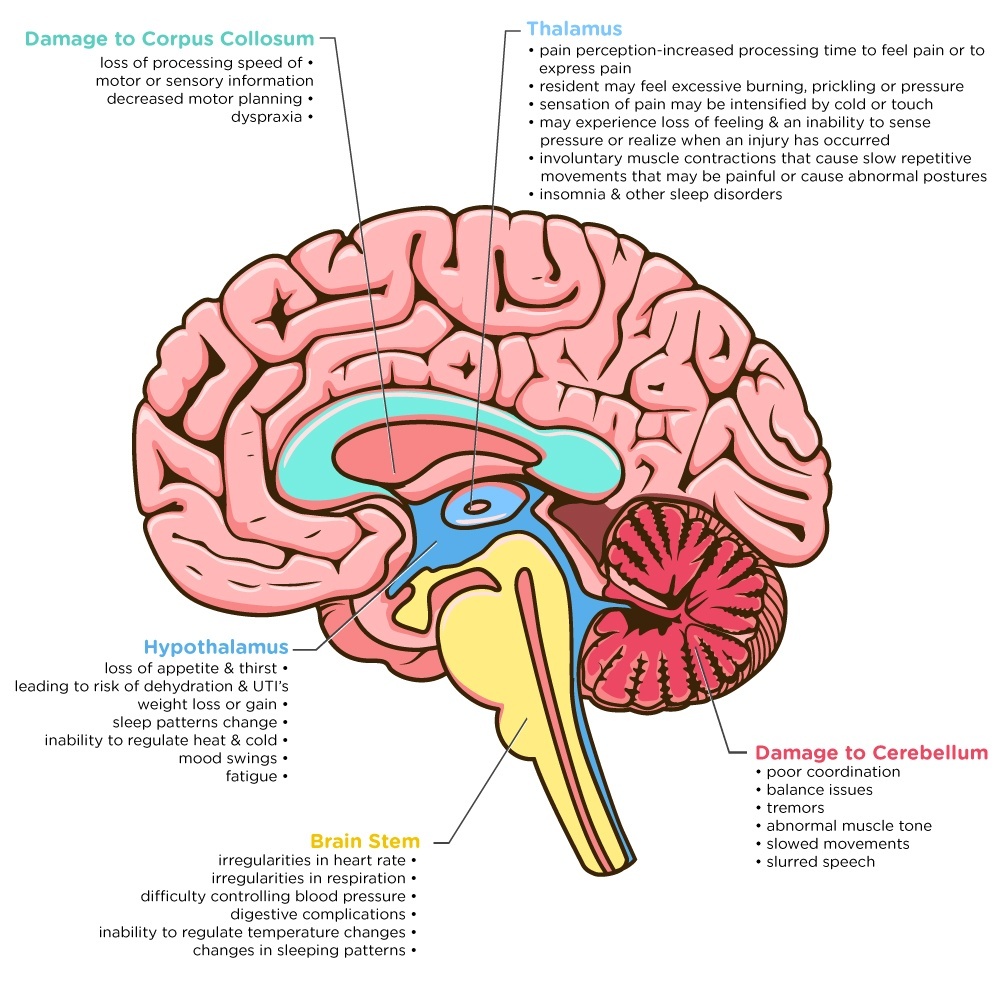

Dementia: What Part of the Brain is Under Attack?

Dementia: Understanding Functional Loss in Your Resident